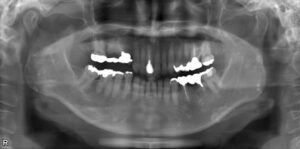

下顎臼歯2本欠損症例

BEFORE AFTER 68歳女性/下2本欠損/インプラント埋込手術 【治療内容】 左下に入っているブリッジからの出血…